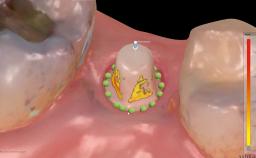

This case from German Gallucci, Adam Hamilton, and Teresa Chanting Sun details immediate placement with a conventional loading protocol (type 1C). It demonstrates a digital workflow combined with risk assessment to determine the best possible treatment approach for replacing mandibular anterior teeth.

A 63-year-old female patient was referred by a periodontist for consultation and assessment with regard to implant rehabilitation of the mandibular incisors. The patient presented in good health with no history of smoking or significant medical history. The patient’s chief complaint was mobility of the mandibular anterior dentition. She had a history of periodontal disease, which had been treated and followed by a periodontist with regular maintenance every four months over the previous ten years.